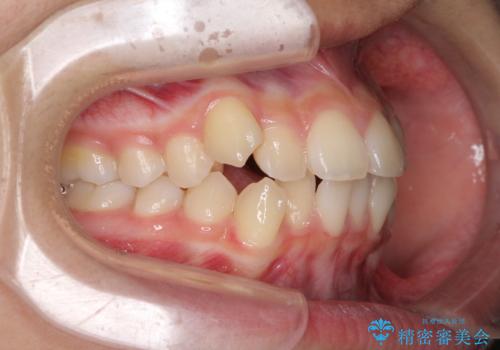

- 前歯のデコボコと八重歯を気にして来院された患者様です。

本人はあまり実感はありませんでしたが、同席されたご家族より口がすぐに開いてしまうことを指摘されていました。

口元に力の入る歯列であったため、上顎左右第一小臼歯4本を抜歯するワイヤー矯正を行うこととしました。